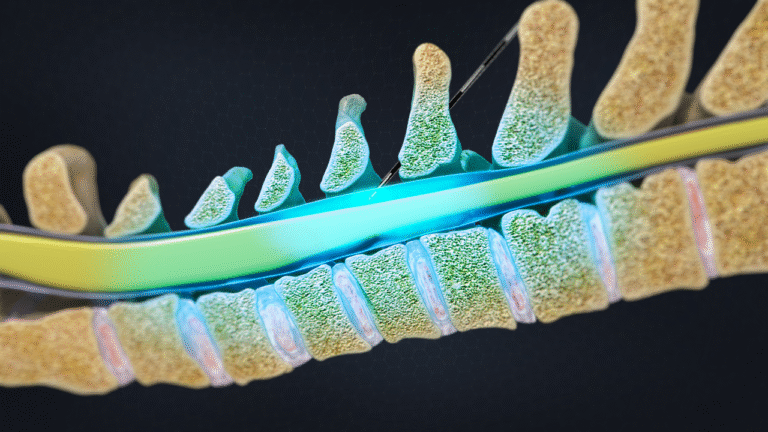

- Procedure mini-invasive

- Neuromodulazione